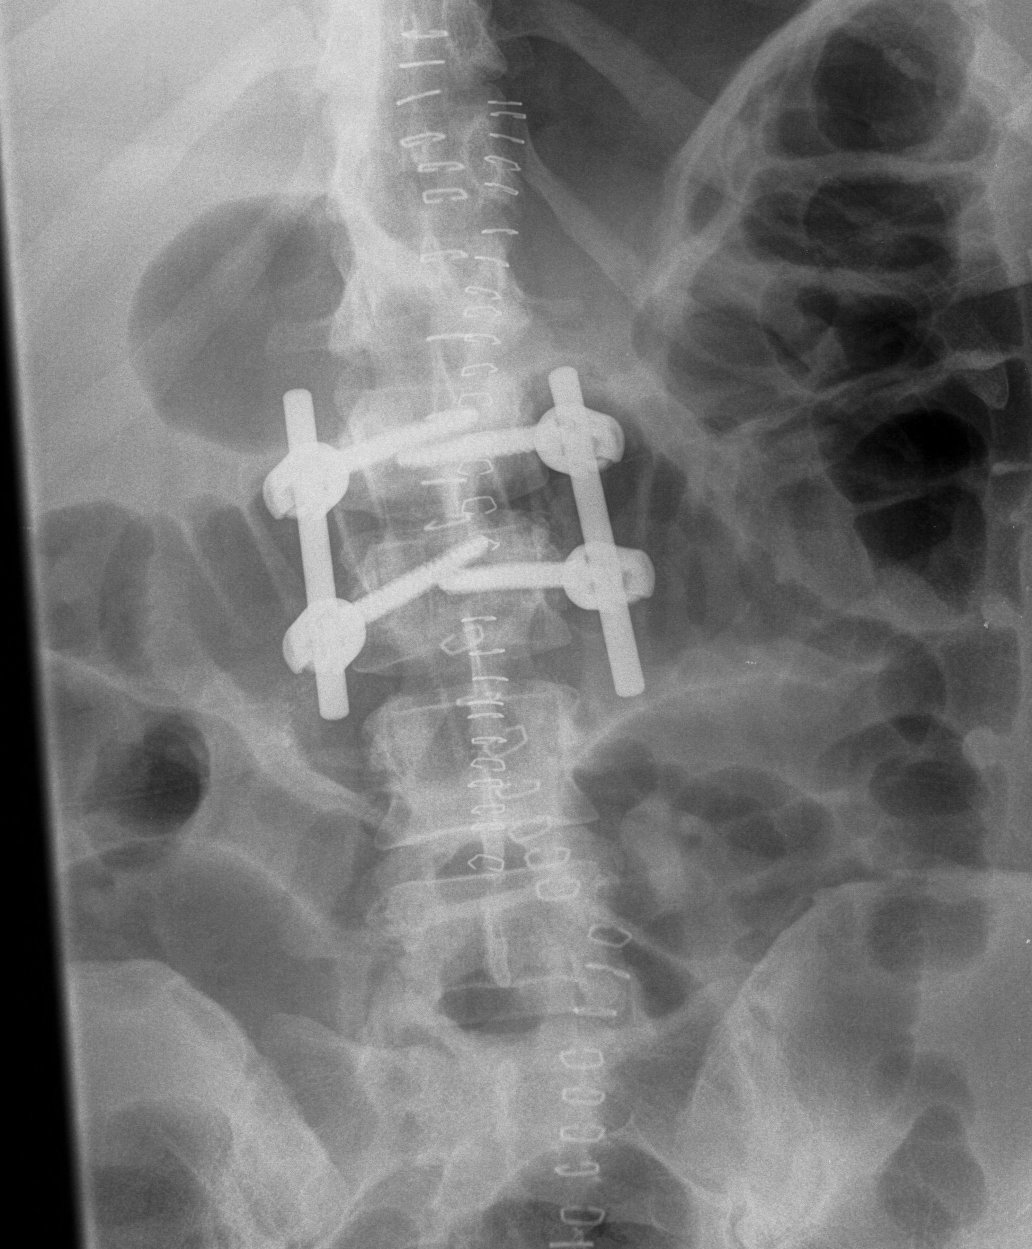

Posterior instrumentation

Indication

- < 7 gaines criteria

- no neurology

Technique

- ligamentotaxis clears canal / PLL acts as bowstring

- pedicle screws lumbar, avoided in thoracic

- use transverse process and pedicle hooks in thoracic

- bone graft inserted via pedicles

- need to do before 5 days post injury